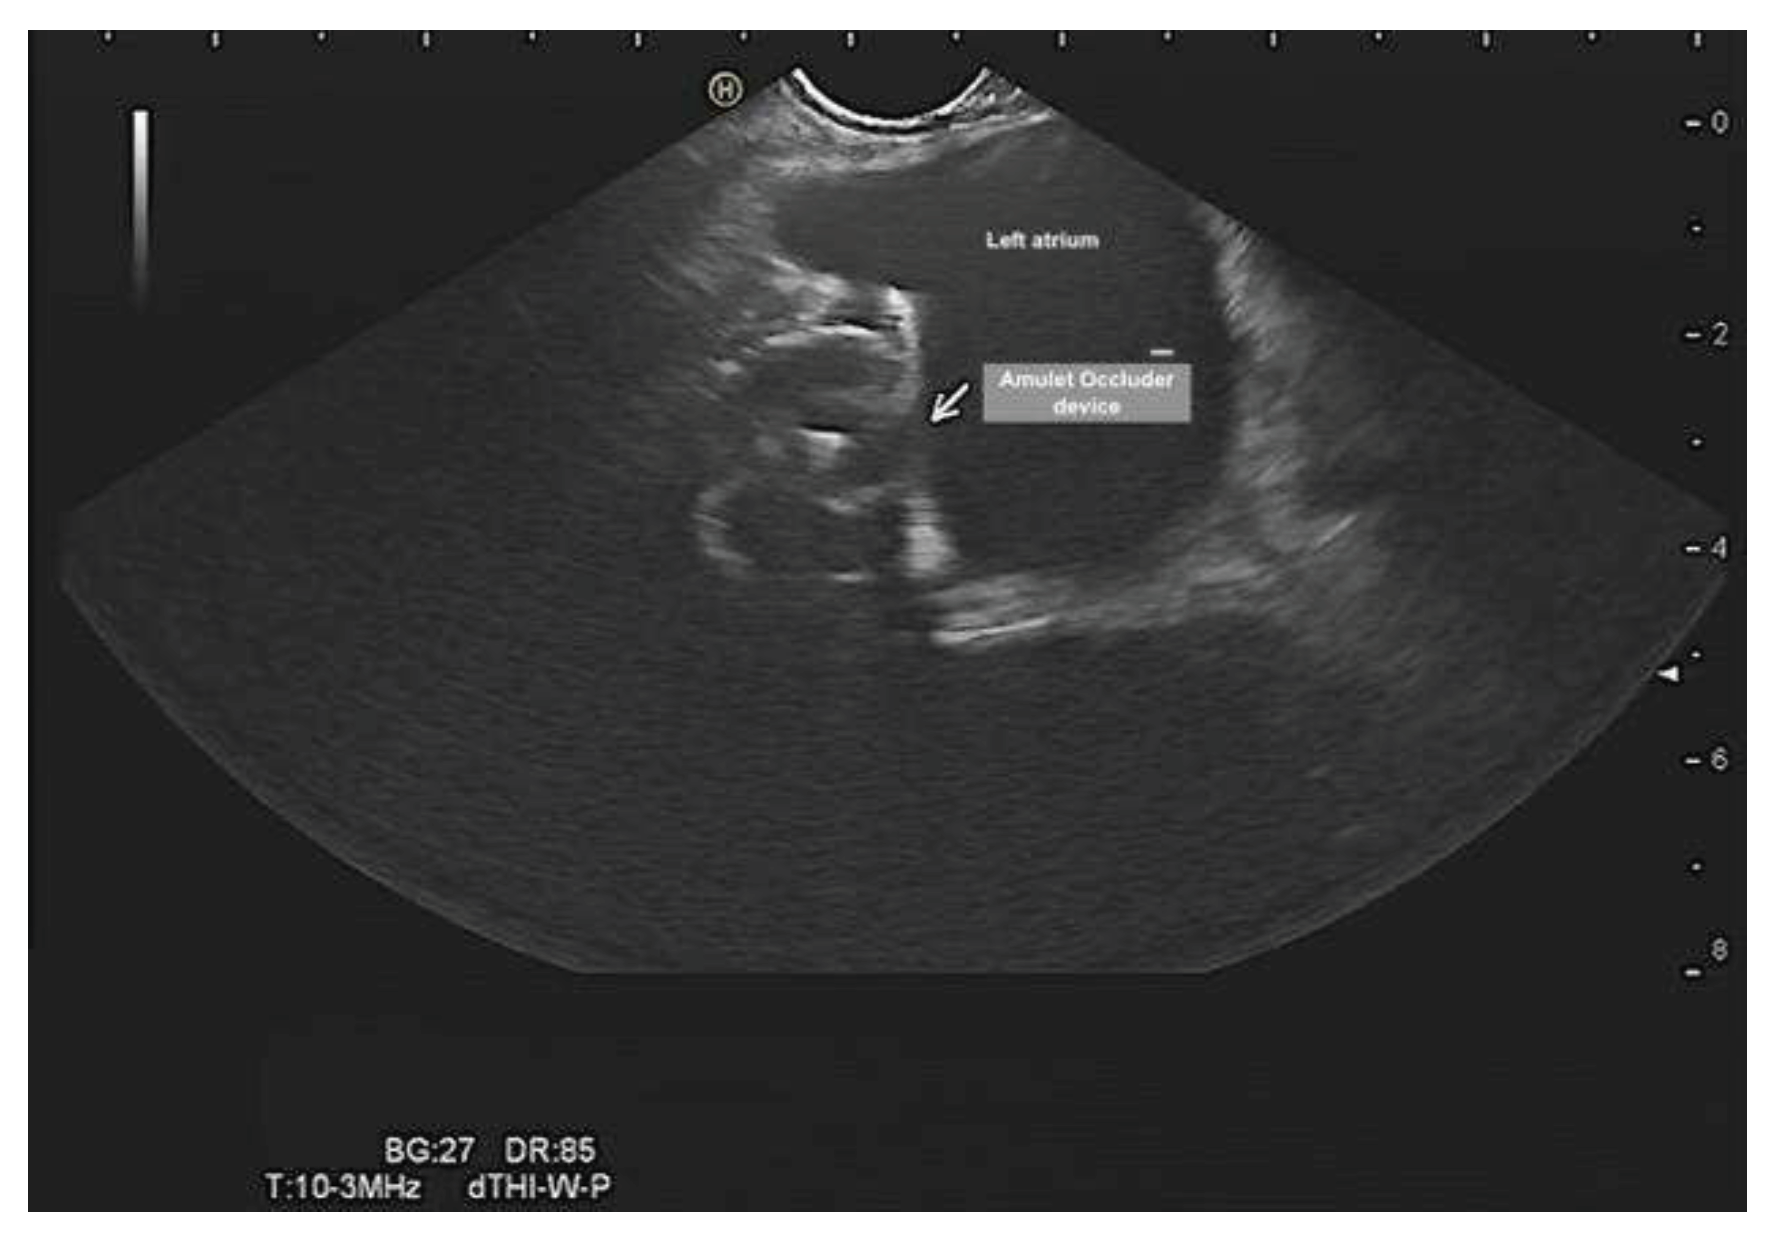

Evalutation of the left atrial appendage occluder, device dislocation, device-related leak, vegetation, or thrombus (Figure 7 and Figure 8). The EUS can provide adequate and precise visualization of the LAA and could complement TOE in LAA evaluation. EUS in this context can (1) rule out LAA thrombus, (2) confirm device stability after release, (3) check for device-related leaks, (4) rule in/out device related thrombus and vegetation (4) monitor complications such as cardiac tamponade.

Percutaneous occlusion of the LAA devices is is a minimally invasive catheter-based therapy. When the device is positioned properly in the appendage, it covers the opening of the appendage. Over time, a thin layer of tissue will grow over the surface of the Amulet device. This keeps any blood clots in the left atrial appendage from entering the bloodstream.Thus, reduces the risk of thromboembolic complications associated with non-valvular atrial fibrillation.

Figure 7. Ultrasonographic ultrasound demonstrated the morphology of amulet occluder device of left atrial appendage without leak, thrombus or vegetation.

Preprints 79537 g007

Figure 8. Ultrasonographic ultrasound demonstrated the morphology of amulet occluder device of left atrial appendage without leak, thrombus or vegetation.